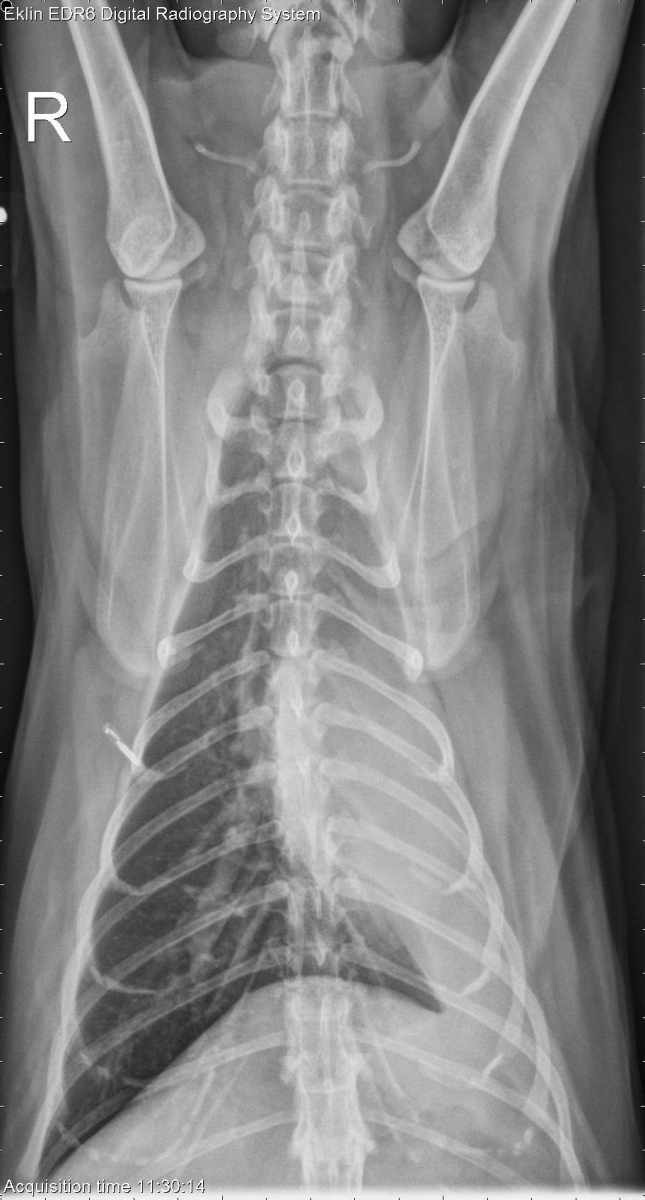

8 year old male neutered Domestic Shorthair with 1 month of anorexia and weight loss. What is the primary problem?

DV Thorax

There is a rounded soft tissue mass superimposed on the heart base on both lateral projections, causing ventral deviation of the carina. On the ventrodorsal and dorsoventral projections, there is a mediastinal shift to the left and atelectasis of the left lung lobes. The right lung lobes are hyperinflated. There is a moderate bronchial pattern throughout the lungs.

• Pulmonary mass causing bronchial obstruction and secondary volume loss in the left lung lobes (neoplasia, abscess, granuloma).

• Pulmonary abscess (Nocardia or Actinomyces)

• The mass was confirmed by ultrasound and a fine needle aspirate was obtained for cytology. No further treatment was pursued.